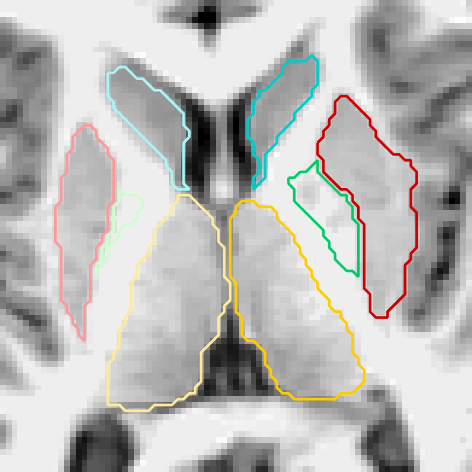

Figures 6 and 3.2 give visual examples of segmentations obtained by our 3D FCNN architecture and standard references contoured by FreeSurfer.

It can be observed that the segmentations generated by our proposed architecture are significantly smoother than those of FreeSurfer, regardless of the subject group (i.e diagnosis, age, site employed or not in training). We also notice that our system is better at identifying thin regions in the structures of interest, for instance, the lower extremities of pallidum (green regions).

Site used in training

FreeSurfer Refer to caption Our CNN Refer to caption Refer to caption Refer to caption

Refer to caption Refer to caption

Figure 6: Visual examples of our 3D FCNN architecture compared with the standard references contoured by FreeSurfer, for three test subjects from sites used in training.